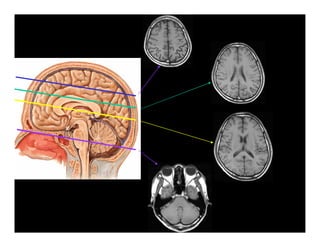

GIẢI PHẪU HÌNH ẢNH

SỌ NÃO

Giải phẫu hình ảnh sọ não

(1): Bao trong

(2): Đầu nhân đuôi

(3): Nhân bèo

(4): Đồi thị

1

2

3

4

5

6

(5): Não thất III

(6): Sừng trán não

thất bên